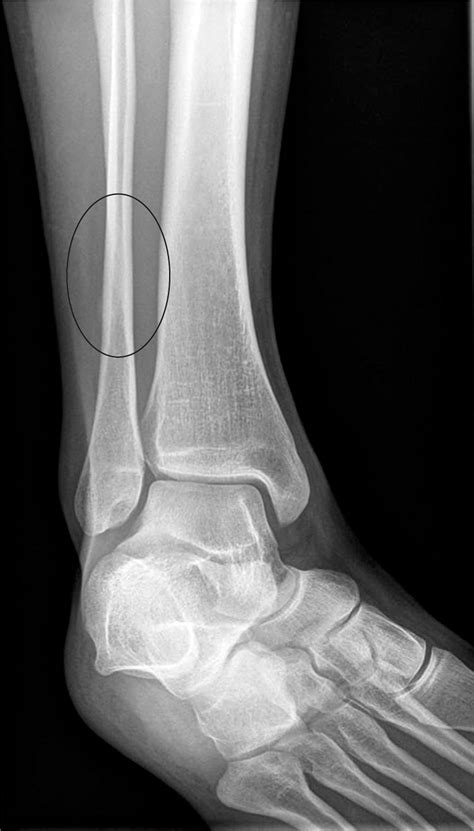

Diagnosing a Stress Fracture Ankle

• Order imaging tests such as X-rays, MRI, or bone scans to confirm the diagnosis.

Imaging tests are crucial because stress fractures may not be visible on initial X-rays. An MRI or bone scan can provide a more detailed view of the bone and surrounding tissues.